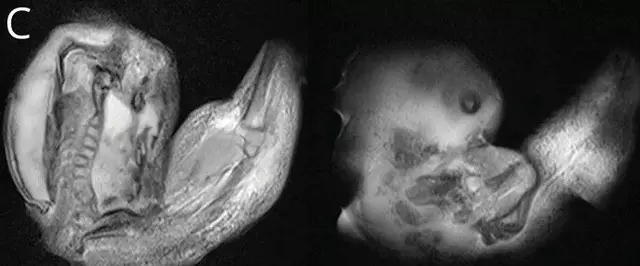

Vaka raporuna göre, araştırmacılar bebeğin kafatasını çeşitli görüntüleme yöntemleriyle incelediklerinde, beyninin sıkıştığını ve sıvı birikimi oluştuğunu tespit etti. Daha sonraki incelemeler ise, bebeğin aslında anne karnındayken bir ikiz kardeşi olduğunu, ancak ikinci bebeğin yeterince gelişemeyerek kardeşinin kafatasının içine sıkıştığını ortaya çıkardı. Doktorlar, fetüsün üst uzuvlarının, kemiklerinin ve hatta tırnaklarının geliştiğini, muhtemelen rahimdeki kardeşinin içindeyken aylarca büyümeye devam ettiğini bildirdi.

Yaklaşık 10 santimlik fetüs, ameliyatla çıkarıldı. Vaka, tıbbi literatürde sadece 18 kez rapor edilen bir durum olarak kayıtlara geçti. Bu olay, tıbbi dünyada oldukça nadir görülen bir fenomeni temsil ediyor. Benzer şekilde, 2015 yılında Çin'de bir erkek bebeğin testisinde doğmamış ikizinin fetüsü bulunmuştu. 20 günlük bebek, doğumun ardından testis torbasının şişmeye başlaması üzerine hastaneye kaldırılmıştı.